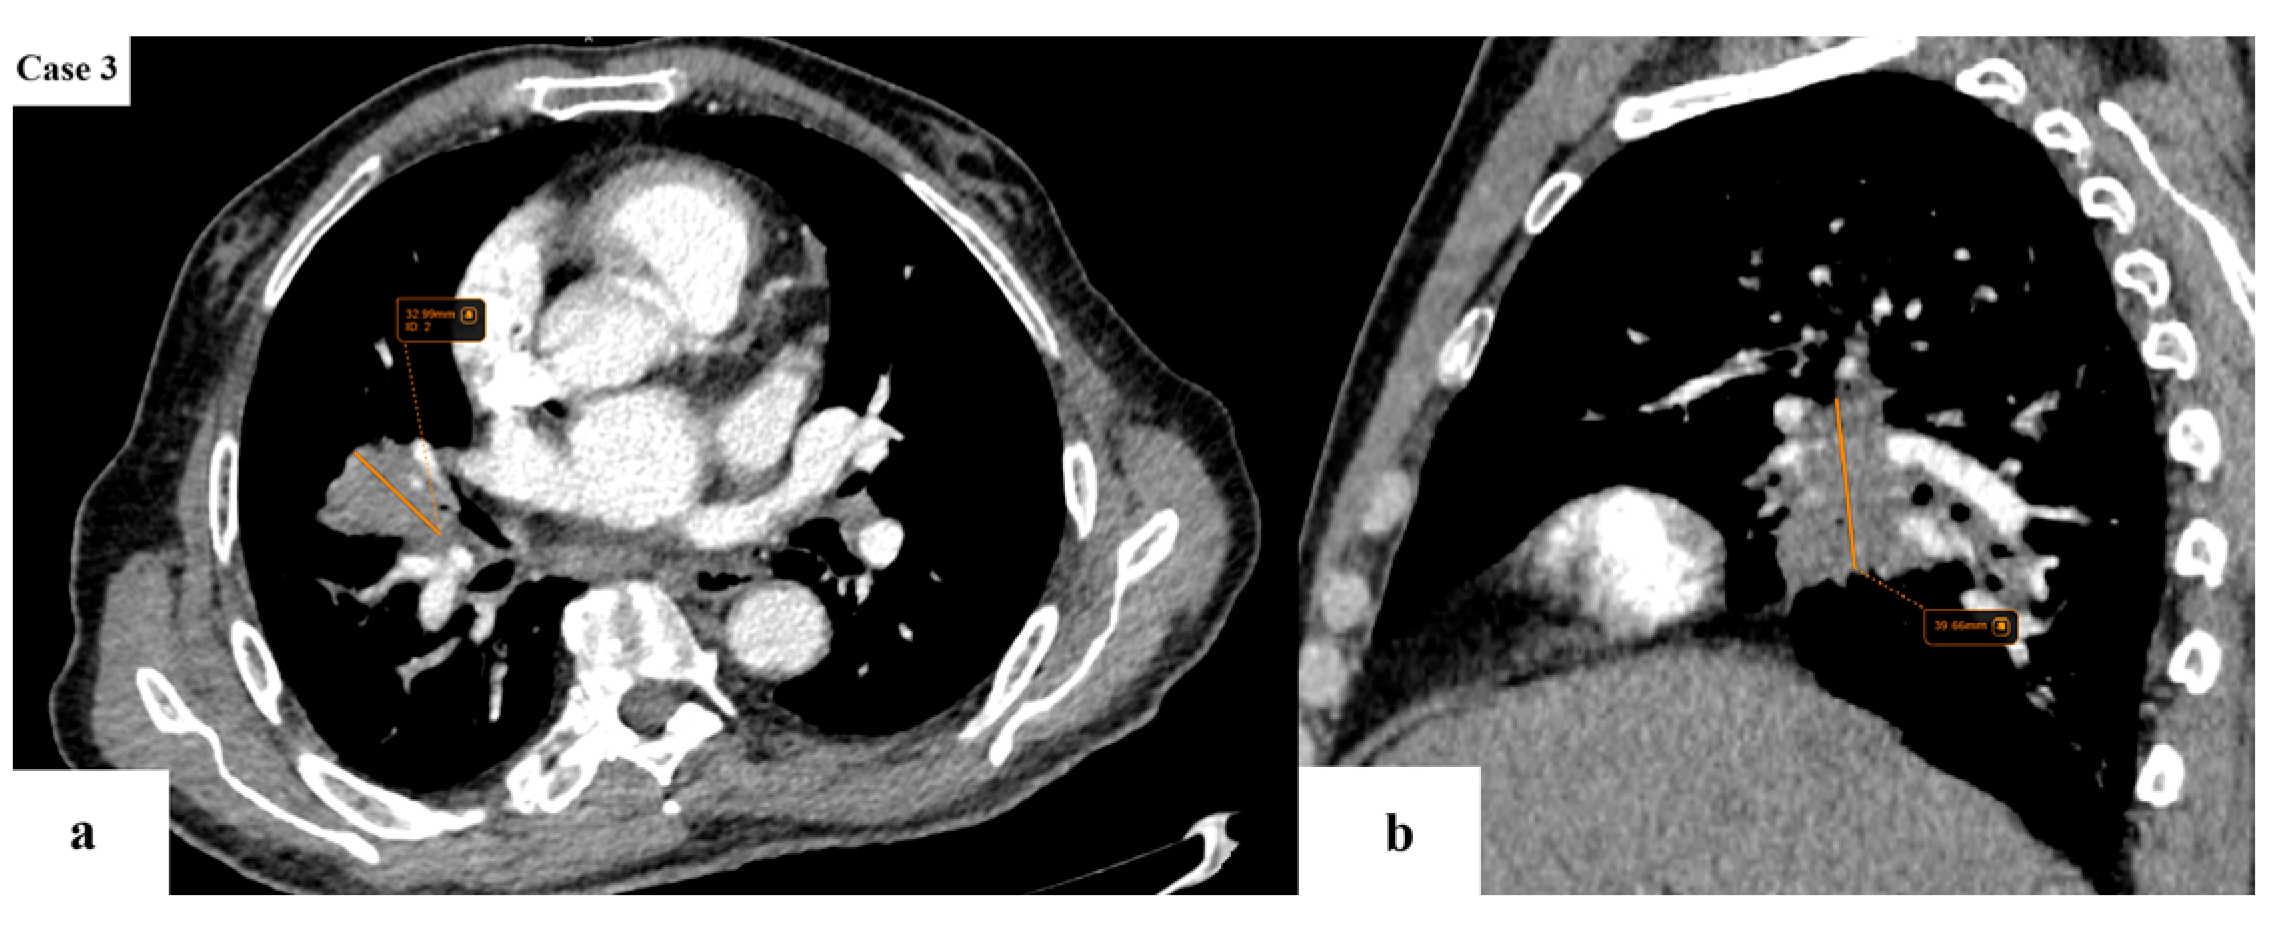

- N descriptor: subdivision of N2 disease into single-station (N2a) and multi-station (N2b);

| Tumor size (cm) | Median 4.2 (IQR 2.6–5.9) |

| Imaging features | Spiculated margins: 88% Central necrosis: 38.4% Cavity: 10.4% Lymphangitic spread: 43.2% |